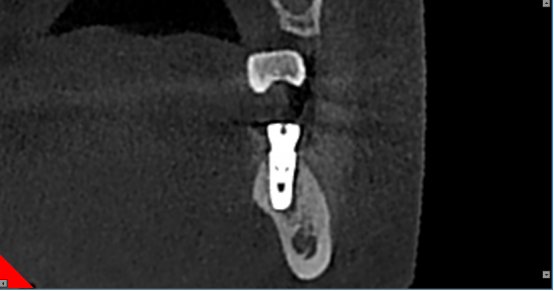

1.提供各种颌面信息及三维图像信息,精确地获得所需术前诊断信息。

2.为种植提供测量颌骨宽度、长度、密度及各种距离、角度等综合信息,以选择各种种植体尺寸及位置。

3.重要结构的定位,种植体间距离安全碰撞检测(神经管、上颌窦、病变位置等)避免手术中发生突发情况。

4.真实模拟种植体的位置,可选择任意种植型号、大小尺寸等,方便医患直观交流讨论。

5.定制手术外科导板,精确定位种植体位置及方向,提供微创及即刻种植方案